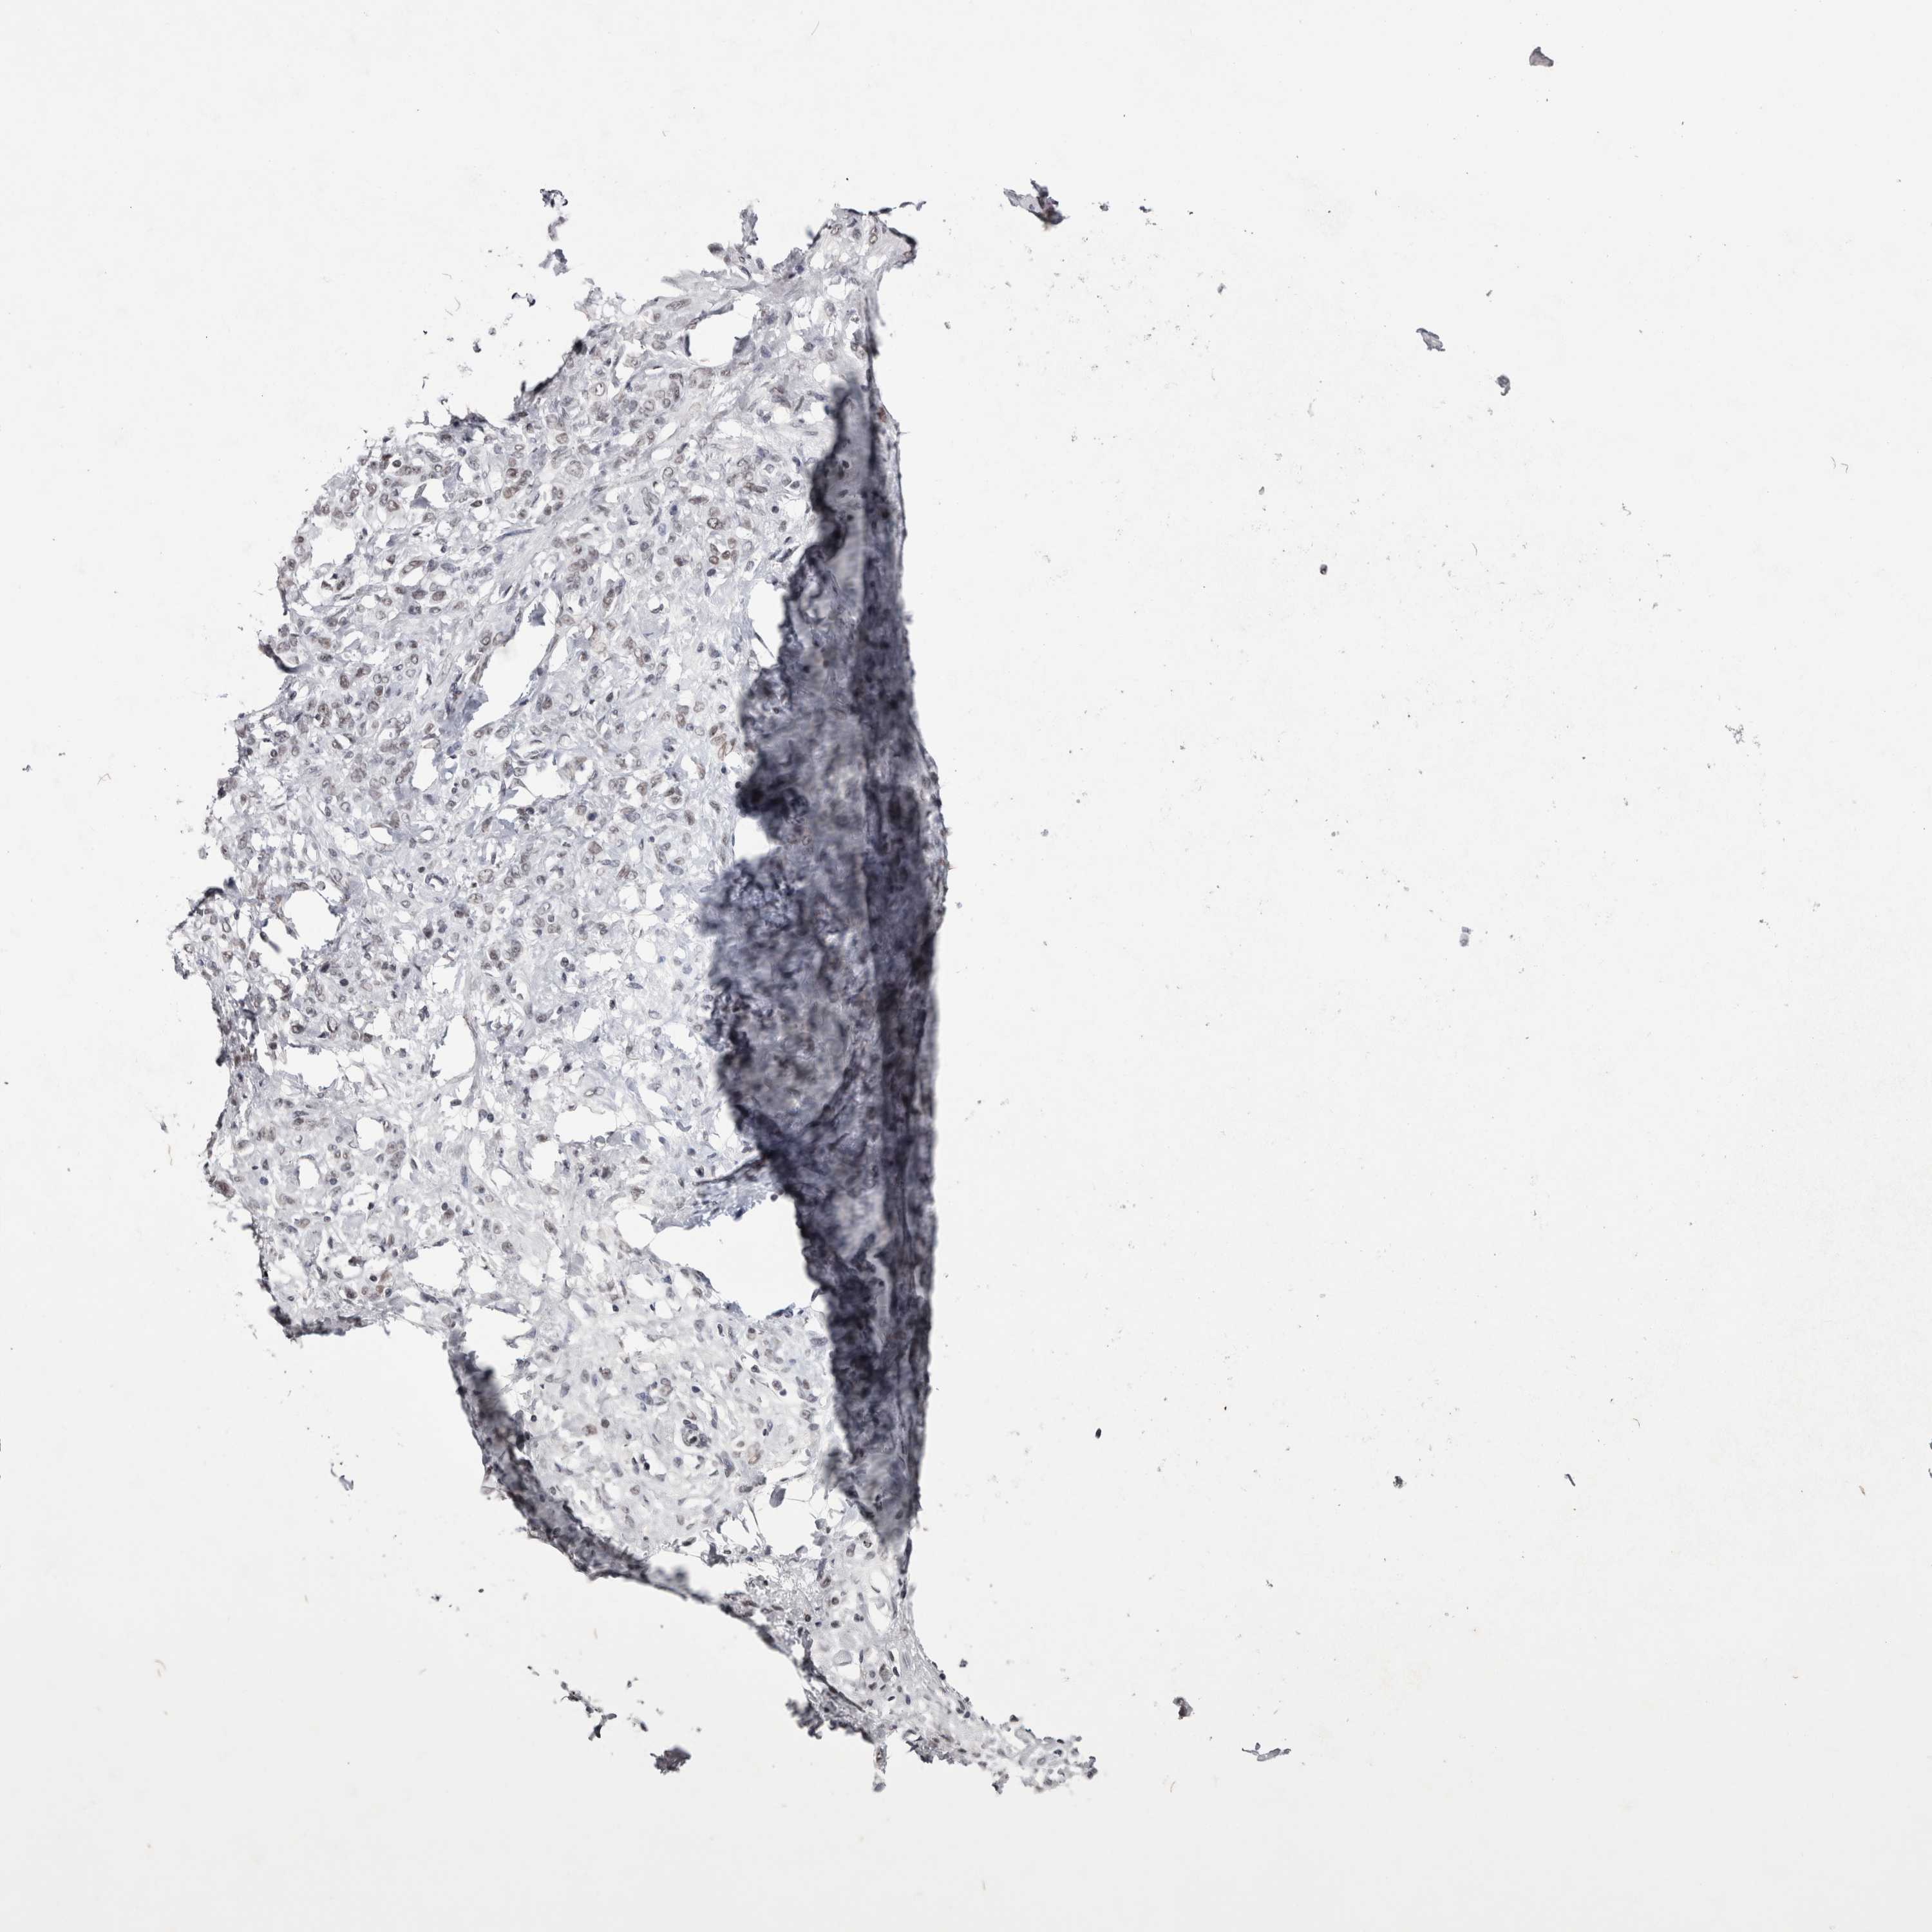

STOMACH CANCER - Protein expressioni

A mouse-over function shows sample information and annotation data. Click on an image to view it in a full screen mode. Samples can be filtered based on level of antibody staining by selecting one or several of the following categories: high, medium, low and not detected. The assay and annotation is described here.

Note that samples used for immunohistochemistry by the Human Protein Atlas do not correspond to samples in the TCGA dataset.

Antibody stainingi

Antibody staining in the annotated cell types in the current human tissue is reported as not detected, low, medium, or high, based on conventional immunohistochemistry profiling in selected tissues. This score is based on the combination of the staining intensity and fraction of stained cells.

Each image is clickable and will lead to virtual microscopy that enables deeper exploration of all samples and also displays staining intensity scores, fraction scores and subcellular localization as well as patient and tissue information for each sample.

Antibody CAB025404

Staining

High

Medium

Low

Not detected

Intensity

Strong

Moderate

Weak

Negative

Quantity

>75%

75%-25%

<25%

None

Location

Nuclear

Cytoplasmic/membranous

Cytoplasmic/membranous,nuclear

Adenocarcinoma, NOS